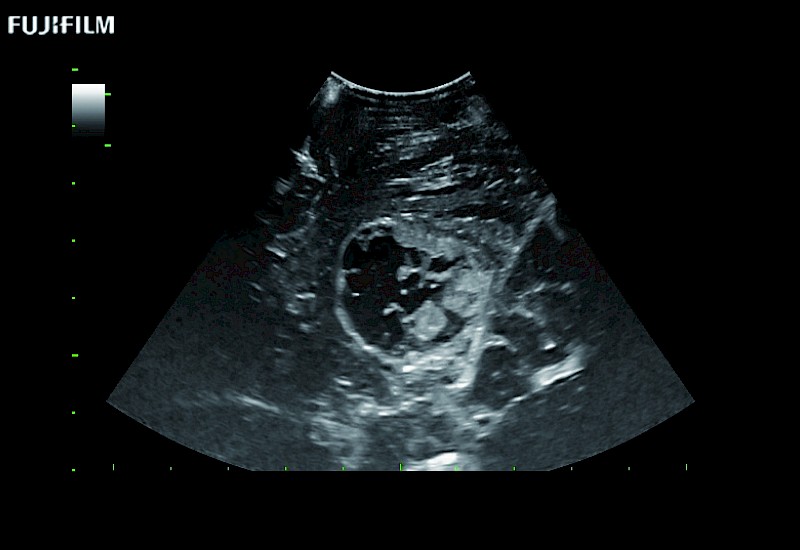

Tight curved (12mm) array transducer that is ideal for scanning during cranial guidance procedures.

The world's only phased array burr-hole transducer that is ideal for scanning during burr-hole guidance procedures.

Smaller footprint (20mm) curved array transducer that is ideal for scanning during cranial guidance procedures.

Guidance is the fundamental purpose for all of our surgical ultrasound technology. Fujifilm Healthcare is committed to designing tools that help neurosurgeons navigate inside the human body and provide the necessary information to immediately make critical surgical decisions.